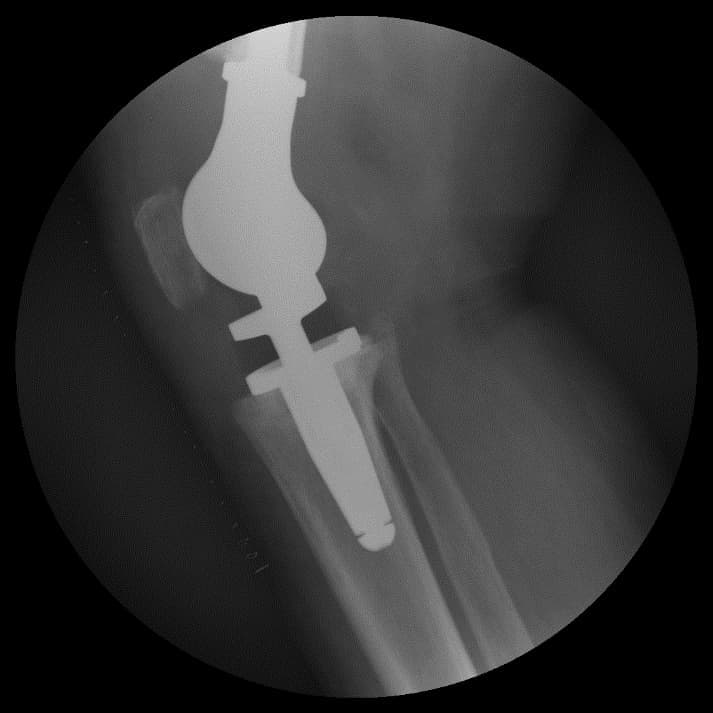

Үе дайрсан ясны анхдагч хавдар, ясны дутмагшлын үед хийгдэх мэс засалimg20Үе дайрсан ясны анхдагч хавдар, ясны дутмагшлын үед хийгдэх мэс засалimg21

Зураг 3. Мэс заслын дараах рентген зураг. Эгц урд, хажуугаас авсан байдал

Энэ тохиолдолд үений шөрмөсөн холбоос хэвийн хадгалагдаж үлдсэн байсан. Хиймэл үе - ястай тогтвортой сайн бэхлэгдэх нөхцлийг хангах чөмөгт гол руу орсон уртасгагч – extension stem-тэй хиймэл үе.